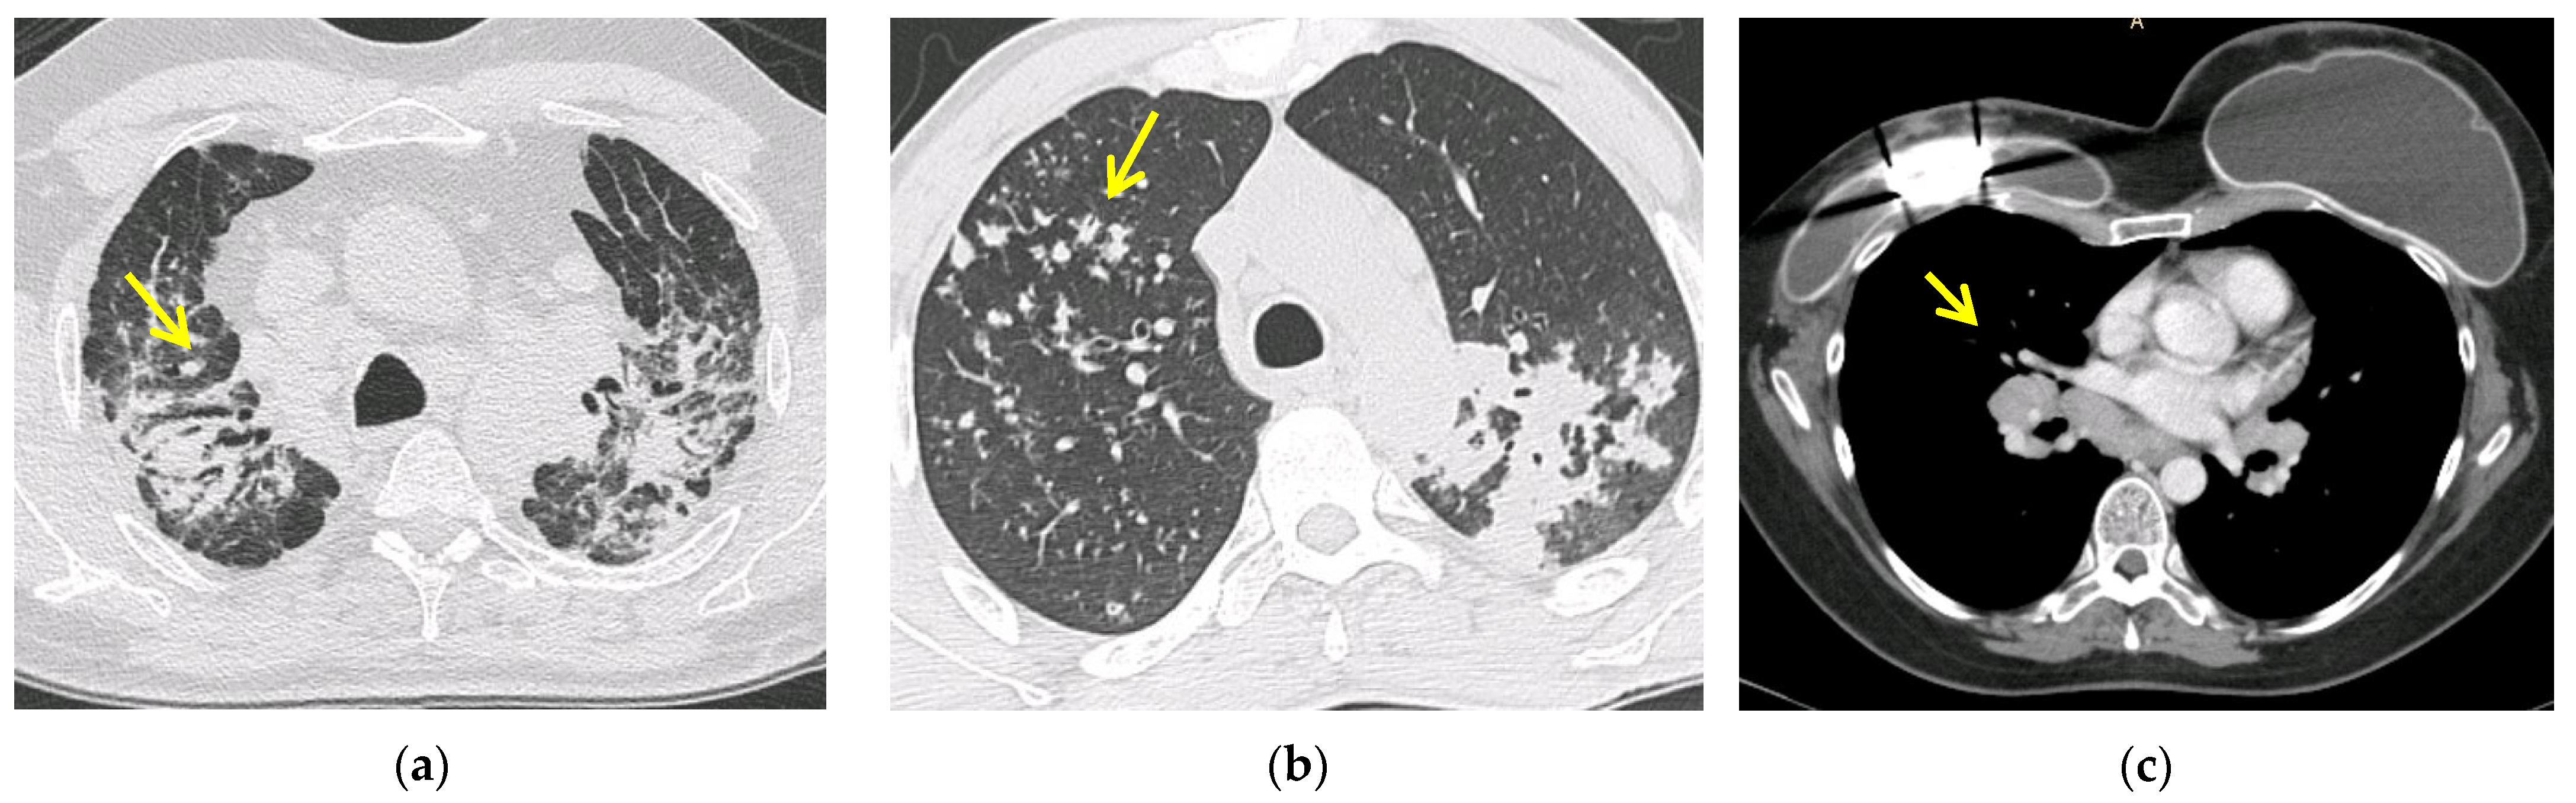

5.2. Computed Tomography (CT Scan)